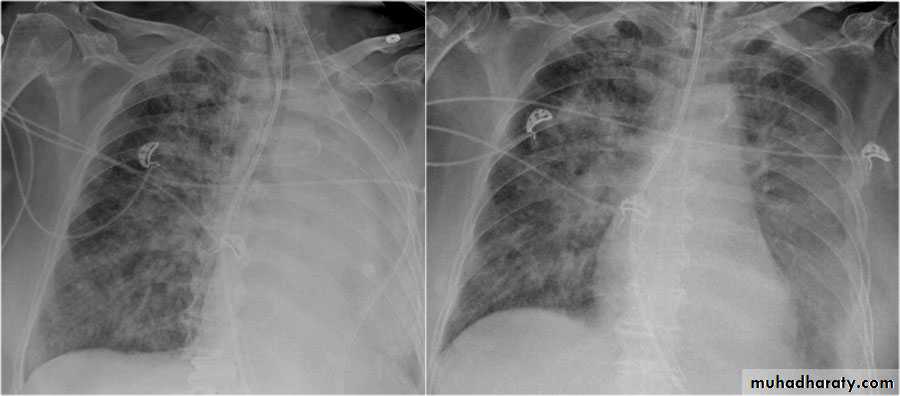

Severe dyspnea with shock